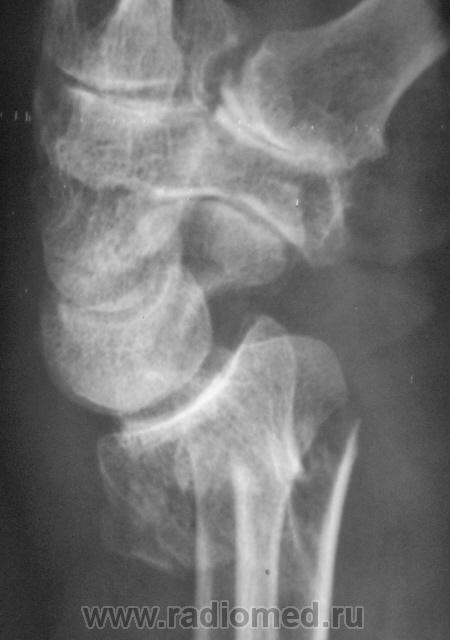

Случай 3. Пациент направлен врачом хирургом на рентгенографию лучезапястного сустава.

А вот по-поводу второго случая: перелом луча в "типичном" месте, только вот смущает ладьевидная кость - какая-то она патологическая, имеется участок разряжения костной ткани в проекции головки кости или я ошибаюсь?